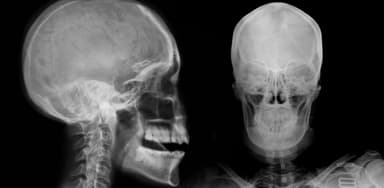

2.3. Chụp X-quang sọ não

Dù không còn được sử dụng rộng rãi trong chẩn đoán u màng não do độ phân giải thấp, nhưng trong một số trường hợp vẫn có thể phát hiện các dấu hiệu gián tiếp như vôi hóa trong u, dày hoặc phá hủy xương sọ, hay giãn rộng các mạch máu nội sọ.